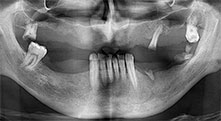

Бихте ли описали накратко, например, Вашия метод за мобилизиране на костни блокове за трансплантация?

Брату: Ние предпочитаме да събираме кост от външната страна на гребена в задната част на долната челюст. След разрязване на меките тъкани, ние използваме новите триони, за да определим количеството кост, което ще събираме. С този подход, ние използваме трионите за цялата препарация в почти 80% от случаите. Може да използваме и други пиезо инструменти и накрая длето за мобилизиране на блока. Ние смятаме, че това е изключително ефективна хирургична техника.

Брату: Ние предпочитаме да използваме техниката "сандвич" за аугментация в страничната долна челюст. Покритие на костта се подготвя с пиезо трион и кресталният фрагмент се фиксира с микровинтове. Поставяме смес от автогенна костна присадка и ксеногенен костозаместител между тях. Това работи много надеждно. Трябва винаги да осигурявате достатъчно оразмерени вертикални срезове при шиниране на алвеоларния гребен в долната челюст. В противен случай, костта лесно може да бъде счупена.